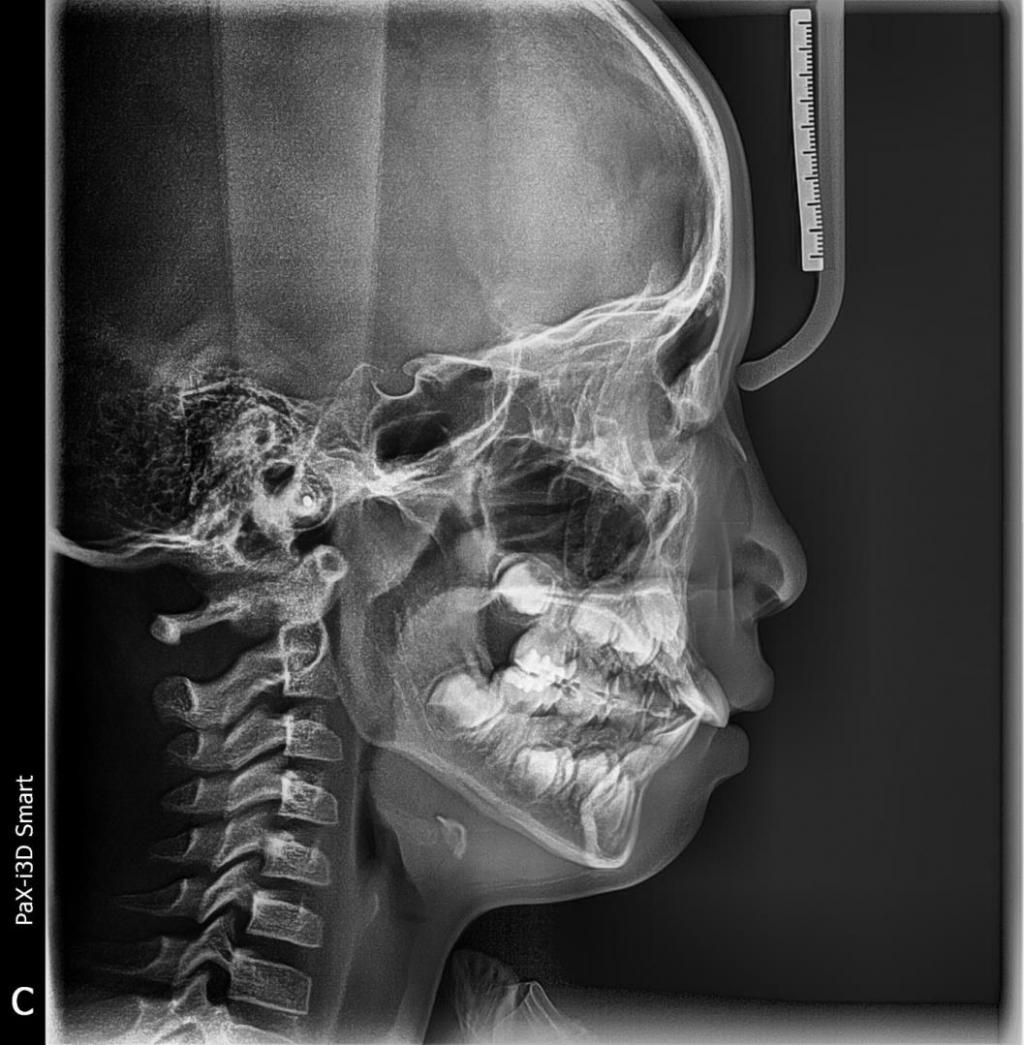

보내주신 두 장의 방사선 사진을 보면 일단 어금니 관계가 안 맞네요.

저 같으면 우선 Headgear를 써서 위 어금니를 뒤로 보내서 어금니 관계를 맞추고 아래 턱 성장을 유도한 뒤 다시 진단을 해서 위아래 작은 어금니 발치 4개를 고려하면서 치료 계획을 세우는 게 좋아 보이네요.

위 턱 확장은 아래 턱보다 좁은 경우에만 유용하고, 위 아래 턱 폭이 맞는데 위 턱만 확장한다는 것은 의미가 없어 보입니다. 그리고 앞니만 배열해서는 큰 그림으로 볼 때는 pre-orthodontic treatment의 효과가 없어 보입니다. 사실은 "프리올소 착용"이란 것이 무엇을 뜻하는 지는 잘 모르겠습니다만.